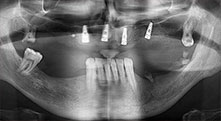

residual dentition

A 40-year-old patient with very poor residual dentition wanted an implant-based restoration. Because he is a smoker, a sinus lift in the maxilla with a fixed denture was contraindicated. A bar denture on four anterior implants was planned.

Piezomed B6

The alveolar ridge was split on both sides by piezo surgery (instrument: Piezomed B6). The implants were placed in the same procedure and the peri-implant bone was additionally built up using the GBR technique.

Implants

The four implants are in situ, as planned. The distal maxillary molars can still be used to fix the lined denture, which was introduced one month after implantation.